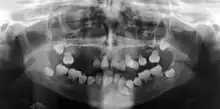

Preoperative panoramic radiographs showing features of dentin dysplasia type I

In other words, affected primary teeth usually have abnormal -shaped or shorter than normal roots. “Crescent/half-moon shaped” pulp chamber remnant in permanent teeth can be seen on x-rays. The roots may appear to be darker or radiolucent/pointy and short with apical constriction. Dentine is laid down abnormally and causes excessive growth within the pulp chamber. This will reduce the pulp space and eventually cause incomplete and total pulp chamber obliteration in permanent teeth.[12][13] Sometimes periapical pathology or cysts can be seen around the root apex.[11] Most cases of DD associated with peri-apical radiolucency/ pathology have been diagnosed as radicular cysts, but some of them have been as diagnosed peri-apical grauloma instead.[14]